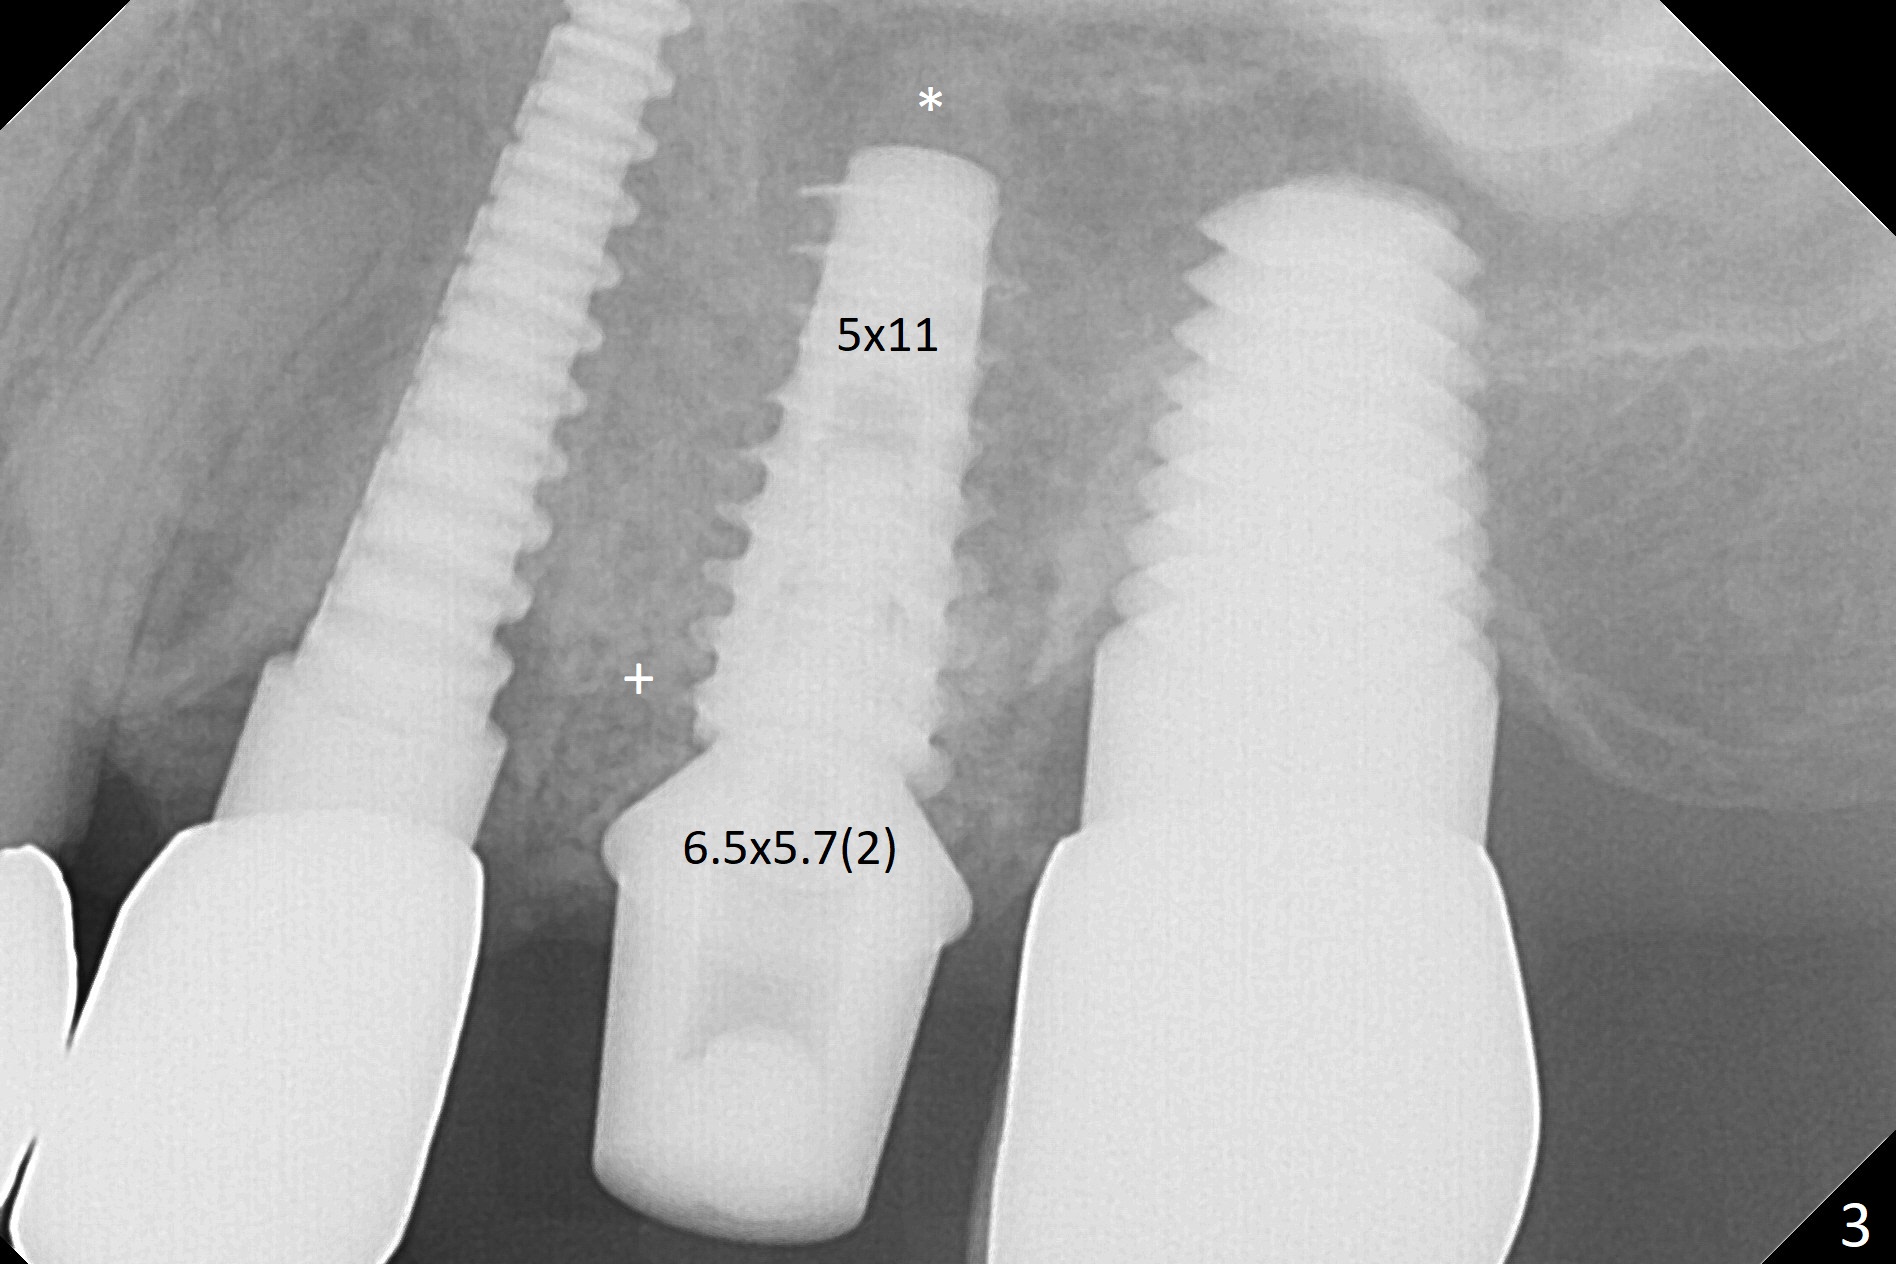

Initial osteotomy in the septum of the tooth #14 is 9 mm, approximately 2 mm from the sinus floor (Fig.1). Subsequent osteotomy depth is 11 mm, followed by insertion of a 4.5x11 mm dummy implant (Fig.2). After use of Magic Drill (MD) 4.8 mm for 9 mm, a 5x11 mm IBS implant is placed with sinus lift without additional bone graft (Fig.3 *). In contrast, autogenous bone (from MD) and Vanilla Graft are meticulously placed in the remaining socket (+) before and after placement of a 6.5x5.7(2) mm abutment. An immediate provisional is fabricated to close the sockets. There is buccal tenderness 1-3 months postop. There is distopalatal implant thread exposure. A healing abutment (5.5x2 mm) is placed. CT confirms thin buccal plate (Fig.4,5). It appears that the implant should have been as palatal as possible. The tenderness remains for the next 2 weeks. When the healing abutment is removed, the implant seems to have been placed shallow, ~ 1 mm subgingival (Fig.6). With local anesthesia, the implant is reversed to clean the coronal threads with Titanium brush and copious irrigation (Fig.7). The implant is then placed ~4 mm subgingival (Fig.8) and slightly subcrestal (Fig.9,10). It appears that the postop bone loss (Fig.9 *, as compared Fig.1,2) makes the implant look to be placed too shallow. When the implant is being placed deeper, the buccal plate feels intact. The early periimplantitis is apparently due to postop bone loss more than buccal placement, although certain degree of buccal bone resorption must occur. A 6x4 mm healing abutment is placed. Left facial swelling develops 2 days post implant elevation (Fig.11,12, as compared to preop (Fig.13)). The left maxillary sinus cloud (Fig.12) appears to be a false positive finding, since the same feature exists prior to implant elevation (Fig.13). Both sinuses look clear prior to implant elevation (Fig.14). Amoxicillin switches to Augmentin and Flagyl, since the patient is reluctant to have the implant removed. Finally the sinus infection is under control. The patient feels left facial swelling 9 months postop (5 months post elevation) and reports left nasal discharge ~ 1 month earlier. There is mild buccal plate tenderness. The implant seems to be buccally placed (Fig.15,16), although there is no significant change radiographically (Fig.17). The implant is removed with bone graft (Fig.18 *). To avoid complication and failure, an immediate implant at the upper 1st molar should be short and placed deep.